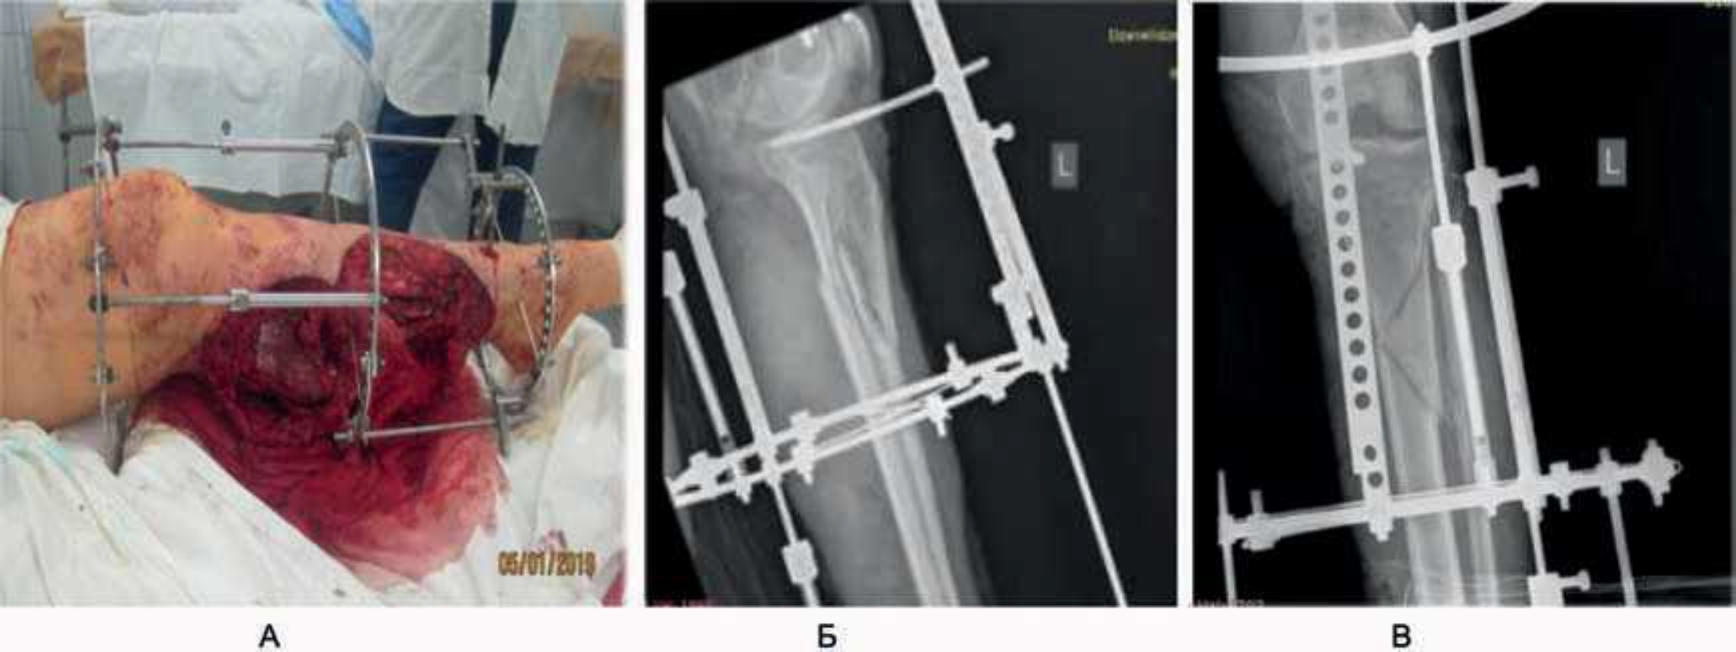

Рис. 5. Состояние на 1-е сутки. 1-й этап операции – металлоостеосинтез (А), рентгеновский снимок после постановки металлоконструкции (Б).

«Автомобильная травма. Открытый оскольчатый (по Густило IIIв) перелом верхней трети левой большеберцовой кости и нижней трети малоберцовой кости. Обширная открытая отслойка кожи левого бедра и голени. Закрытая ограниченная отслойка кожи по наружной поверхности правой голени» (рис. 10). Этапы хирургического лечения представлены на рис. 11, 12, результат восстановления кожного покрова – полное приживление трансплантата – на рис. 13. В течение 1 года пациентка носила компрессионное белье, занималась реабилитацией, в результате – восстановление движения в суставах левой нижней конечности в полном объеме (рис. 14).

Рис. 11. 1-е сутки: 1-й этап операции – металлоостеосинтез. Установка металлоконструкции (А), рентгеновский снимок, прямая (Б) и боковая проекция (В).